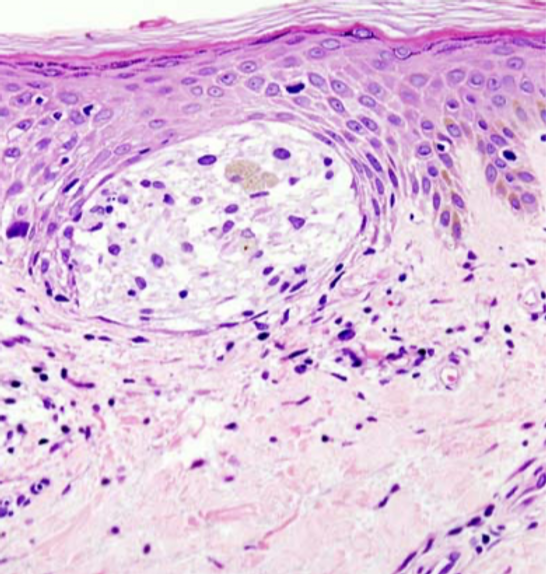

Das Leistungsspektrum umfasst die gesamte histopathologische und immunhistochemische Diagnostik dermatologischer Erkrankungen – von häufigen entzündlichen Dermatosen bis hin zu komplexen, seltenen und neoplastischen Befunden.

Einen besonderen Schwerpunkt bildet die Dermatopathologie der Hauttumoren, einschließlich differenzierter Tumorklassifikation, Prognoseeinschätzung und therapierelevanter Zusatzdiagnostik.